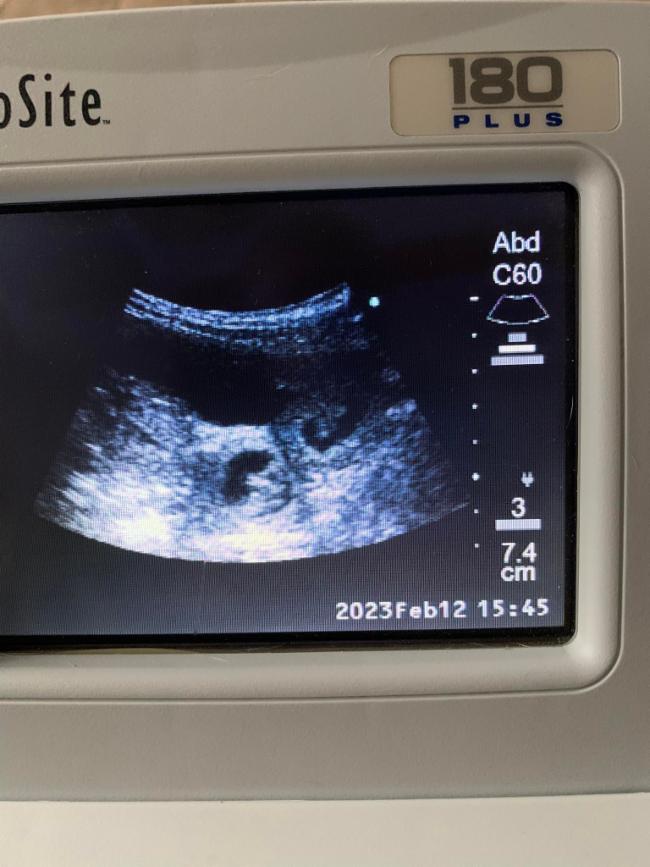

12.02.2023 Juhu, wir sind schwanger!!! <3

13.02.2023 Melodie am 31. Tag der Trächtigkeit!

Ein kleines Bäuchlein ist schon zu sehen, ihr Hunger ist deutlich gestiegen und auch ihr Schlafbedürfnis. Draußen ist sie aber immer noch flott unterwegs. Der Bauchumfang beträgt jetzt 65 cm